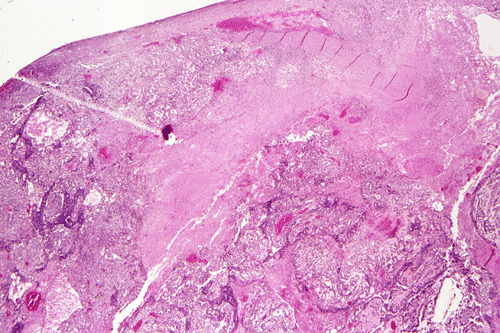

Histopathology of surgical specimen:

A survey at low-magnification shows a necrotic neoplasm (Panel F). The tumor cells arrange in different patterns. The tumor cells are densely packed in some areas but loosely packed in other areas.  At medium-magnification, several different patterns of architecture are disclosed. The most commonly encountered pattern in this case is a reticular-microcystic arrangement of cells (Panel G). In a significant amount of other areas, there are hypocellular to myxoid non-neoplastic stroma lined by a single layer of neoplastic cells (Panel H, I). The tumor cells have moderate to large nuclei with substantial pleomorphism. The chromatin is clumpy and hyperchromatic (Panel J). In some areas the tumor cells has an hepatoid appearance featured by a smaller nuclei with substantial amount of amphophilic cytoplasm (Panel K). Schiller-Duval bodies are occasionally noted (Panel L). A variable number of eosinophilic globules are also present and they are strongly positive for periodic acid-schiff (PAS) reaction (Panel M). Results of immunohistochemistry are as follows:

Mediastinal non-teratomatous germ cell tumor almost always presents as an anterior mediastinal mass 3. Macroscopically, mediastinal germ cell tumor is a large and soft mass with the size of ranging from 6 to 20 cm in greatest dimension. The cut surface is homogeneous, freshy, and decorated by areas of hemorrhage and necrosis. They are unencapsulated and have inconspicuous boundary. Invasion of the surrounding mediastinal structures is a frequent intraoperative finding. In uncommon cases, mediastinal seminoma may be accompanied by extensive fibrosis. Histologically, mediastinal germ cell tumors have features similar, if not identical, to their gonadal counterparts. Here, we will restrict our discussion to yolk sac tumors.